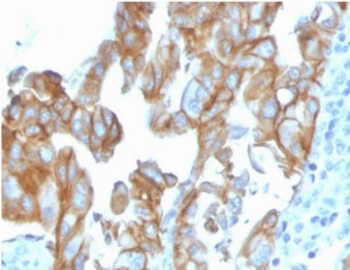

IHC staining of FFPE human colon carcinoma with MerTK antibody (clone TPKR-1). HIER: boil tissue sections in pH9 10mM Tris with 1mM EDTA for 10-20 min and allow to cool before testing.